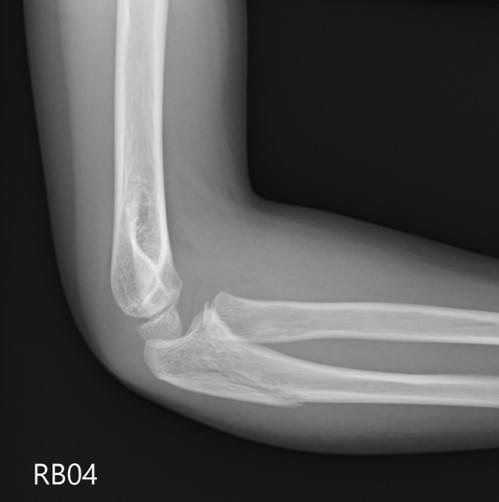

Supracondylar fracture

注意是否有posterior fat pad sign.

Anterior humeral line是否穿過capitellum正中間

評估:

- 除位移程度外,一定要評估是否有神經血管受傷。注意是否有AIN /Ulna nerve/ radial nerve injury或無法摸到radial artery. 如無法評估,病歷上要註記無法評估。

治療:

- 除非type I,其他建議需要CRPP

- 打石膏一定要告知compartment syndrome的風險,一般小朋友打完石膏都會進步很多,如果更痛,一定要認為是compartment syndrome,要馬上鋸開石膏。

- 手術同意書要寫上神經血管及compartment syndrome分險。